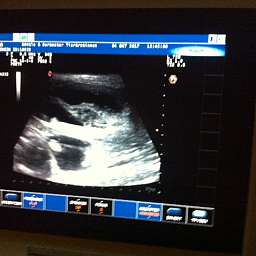

4.10.2017, 35.Tag: Der Ultraschall brachte 5 kleine Wunder zutage. Gesund und munter mit Herzschlag und Bewegung. Elise meisterte alles mit Bravour. Mit Ruhe, Vertrauen und Engelsgeduld ließ sie alles über sich ergehen. Ich bin sehr stolz auf unsere Kleine. Es sind also mindestens 5 Welpen unterwegs. Schaut doch mal: